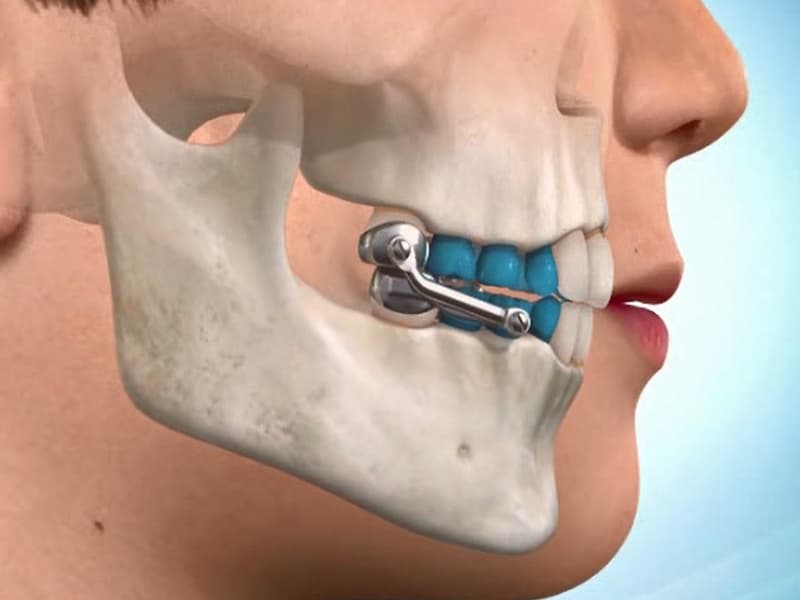

۱. استحکام: ایمپلنت جراح فکی با استفاده از یک فیکسچر وارد شده در آب مشترک فک در بیشتر موارد استحکام بالایی به دندان مصنوعی می دهد.

۲. طبیعیت: به دلیل مواد استفاده شده در ساخت ایمپلنت، آنها بسیار شبیه به دندانهای طبیعی هستند و به راحتی قابل تطبیق با دندانهای اصلی می باشند.

۳. ماندگاری: ایمپلنت جراح فک بعد از جایگزینی به طور دائمی در دهان باقی می ماند و نیازی به خارج کردن و نصب مجدد ندارد.